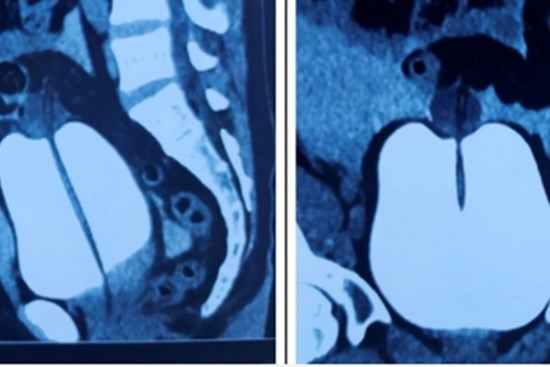

Người phụ nữ đã được đưa đi cấp cứu vì bị vỡ bàng quang trong phúc mạc do tự té sau khi uống rượu, bia quá mức.

Một phụ nữ 46 tuổi đã lâm vào tình trạng nguy hiểm vì bàng quang bị bục do áp suất trong ổ bụng tăng sau khi ngộ độc hải sản